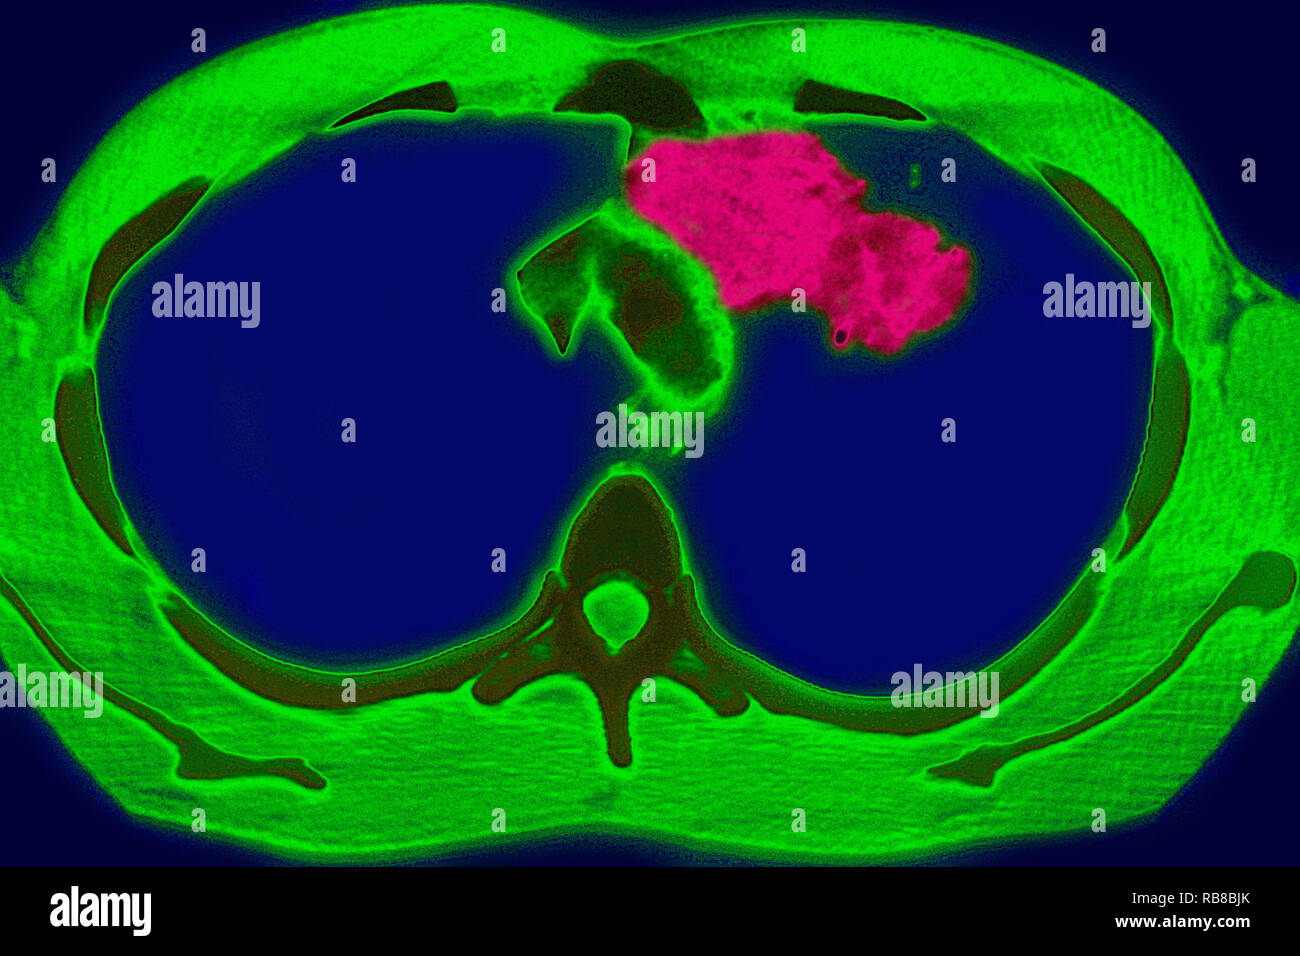

RM2RF8HPX–Pneumonie du poumon droit (infection respiratoire aiguë) révélée par une radiographie thoracique frontale.

RM2RF8HR9–Pneumonie du poumon droit (infection respiratoire aiguë) révélée par une radiographie thoracique frontale.

RM2RF8HPN–Pneumonie du poumon droit (infection respiratoire aiguë) révélée par une radiographie thoracique frontale.